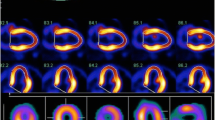

Input function was assessed from the time–activity curve drawn in the left atrium on dynamic PET images. Based on a three-compartment model, parametric maps were computed using a non-linear least squares fitting method pixel by pixel, with the correction of spillover from cardiac chambers to the myocardium [23] (Fig 1).

The value of k4 was assumed to be zero. The LV myocardium was divided into eight segments. The eight regions of interest (ROIs) for each case were drawn manually on the basal anterior, apical anterior, basal septum, apical septum, basal inferior, apical inferior, basal lateral, and apical lateral wall. The values of K1, k2, and k3 were calculated for each ROI. MGU was calculated using the formula shown below. A blood sample was collected at the time of FDG injection to measure plasma glucose level, which was used for MGU calculation.